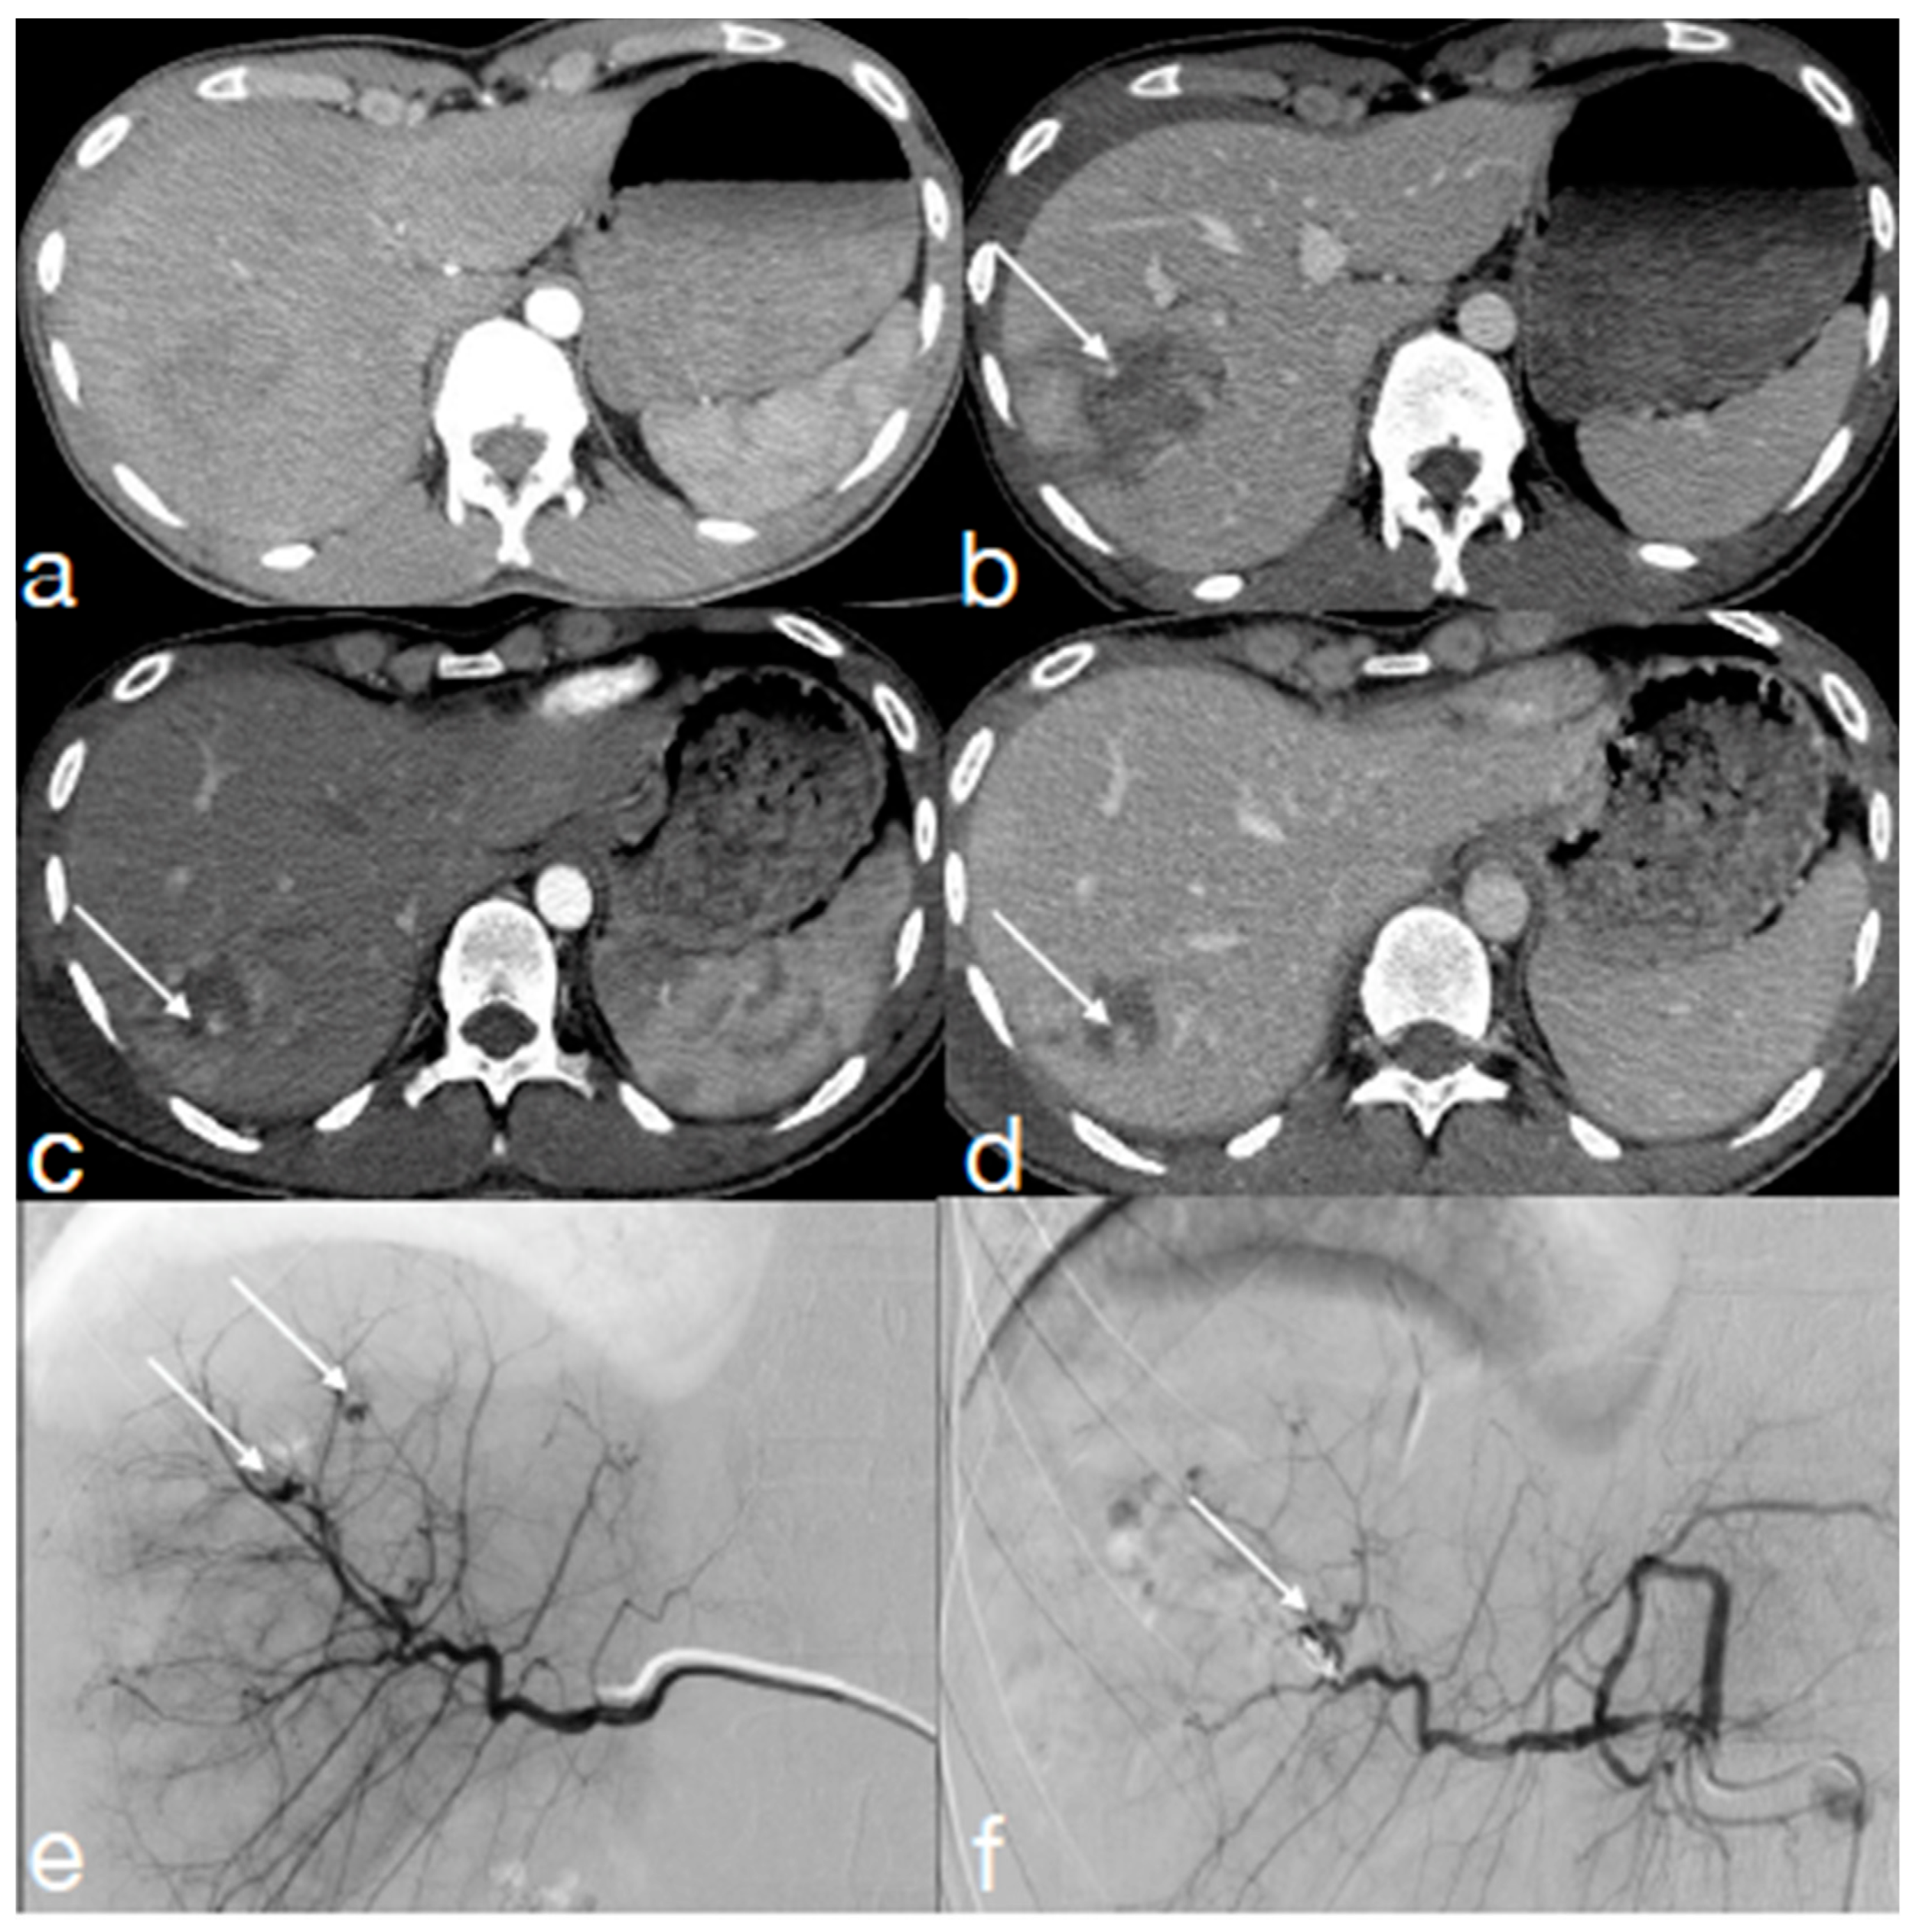

- Iacobellis, F.; Iacobellis, F.; Scaglione, M.; Scaglione, M.; Brillantino, A.; Brillantino, A.; Scuderi, M.G.; Scuderi, M.G.; Giurazza, F.; Giurazza, F.; et al. The additional value of the arterial phase in the CT assessment of liver vascular injuries after high-energy blunt trauma. Emerg. Radiol. 2019, 26, 647–654. [Google Scholar] [CrossRef]

- Uyeda, J.W.; LeBedis, C.A.; Penn, D.R.; Soto, J.A.; Anderson, S.W. Active Hemorrhage and Vascular Injuries in Splenic Trauma: Utility of the Arterial Phase in Multidetector CT. Radiology 2014, 270, 99–106. [Google Scholar] [CrossRef] [PubMed]

- Brillantino, A.; Iacobellis, F.; Festa, P.; Mottola, A.; Acampora, C.; Corvino, F.; Del Giudice, S.; Lanza, M.; Armellino, M.; Niola, R.; et al. Non-Operative Management of Blunt Liver Trauma: Safety, Efficacy and Complications of a Standardized Treatment Protocol. Bull. Emerg. Trauma 2019, 7, 49–54. [Google Scholar] [CrossRef] [PubMed]